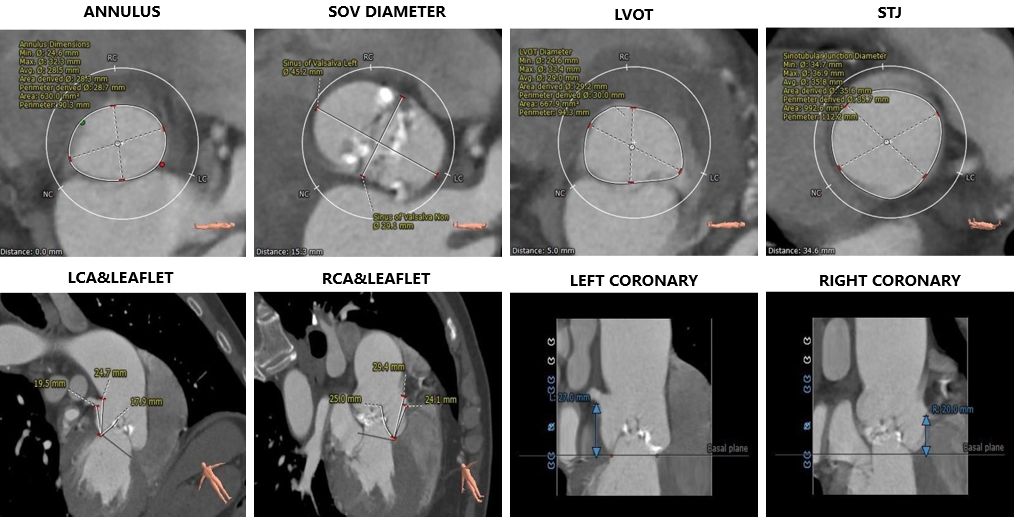

术前评估:

1. Type0型二叶式主动脉瓣,左右冠不同窦,瓣叶中重度钙化伴严重增厚,钙化分布基本均匀,主要分布在瓣叶边缘及管壁附着缘。

2. 瓦氏窦、窦管交界内径可,升主动脉扩张;冠脉散在钙化。

3. 冠脉开口高度尚可,切线位右冠瓣叶长度稍>冠脉开口到瓣叶根部附着缘距离。

4. 瓣环水平夹角75°,横位心,主动脉弓部宽度可、角度稍偏小,升主、弓部、降主动脉扭曲;左室内径可,室壁增厚。

5. 双侧髂动脉扭曲,左髂总局部扩张,股动脉穿刺区域未见钙化斑块,股动脉直径良好 。

主动脉根部评估:

瓣上评估

外周血管及主动脉弓解剖: